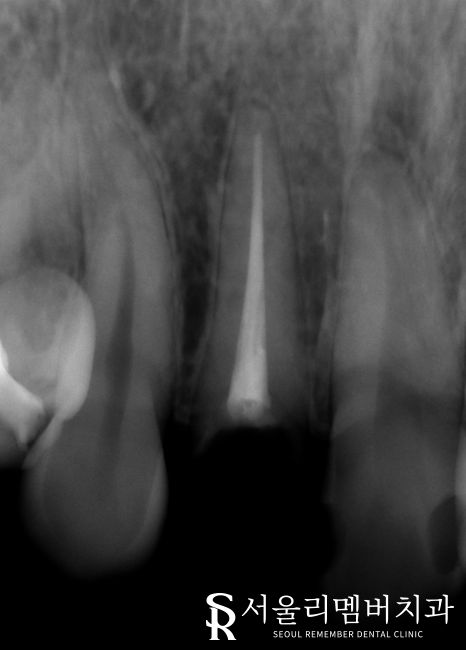

자세히 살펴보니 이곳은

신경치료를 받았던 곳이였는데요.

근관 내부를 채우고 있는 충전재가 관찰 되었습니다.

신경치료를 받았던 곳에 병소가 나타나

전체 치아를 약하게 만든 것은 물론이며 약간의 염증도 동반되었습니다.

이상태로 보존치료를 진행하더라도 보철의 예후 및 수명이 길지 않겠다는 판단이 들었는데요.

따라서 리멤버에서는 # 12 앞니 임플란트를 진행하여 개선을 돕기로 최종 계획을 세웠습니다.